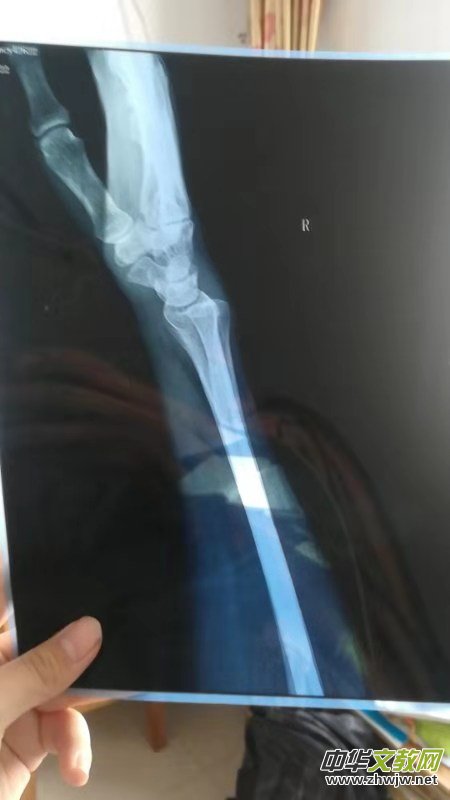

近日我們接到河南安陽李女士多次投訴,說她于2019年2月15日(正月十一)下午在安陽沃爾瑪紅旗路店因踩到地面污物而滑倒摔傷導(dǎo)致右手骨折,當(dāng)時(shí)商場派人一起去醫(yī)院就醫(yī)。在中醫(yī)院拍片后醫(yī)生說骨折要打石膏,然后一周內(nèi)復(fù)查。因家中尚有老母親和上學(xué)的孩子,李女士沒有住院治療,而是留在家中靜養(yǎng),并請姐姐過去照管。2月21日,李女士打電話給商場張經(jīng)理,約好在中醫(yī)院見面,李女士的愛人請假一同打車前往,在醫(yī)院門口等候時(shí)張經(jīng)理來電說有會(huì)議安排,協(xié)商后派其他人員陪同前往醫(yī)院,復(fù)查時(shí)醫(yī)生說如果恢復(fù)不好也有可能造成殘疾,當(dāng)時(shí)商場陪同人員醫(yī)藥費(fèi)都沒負(fù)責(zé),說是接到領(lǐng)導(dǎo)電話看監(jiān)控李女士是被人撞倒摔傷不完全是商場責(zé)任,李女士只得先墊付了藥費(fèi)。